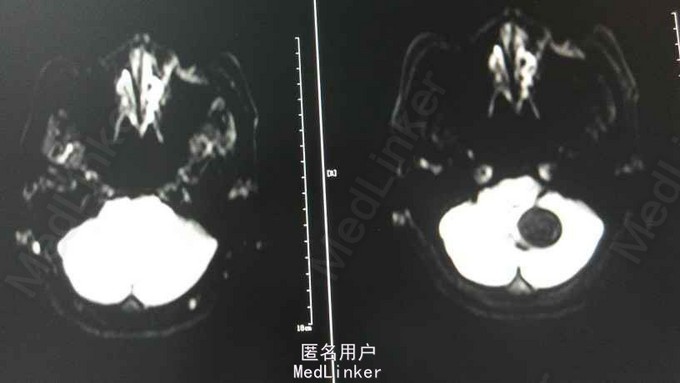

查体:T 36.5℃,P 81bpm,R 18bpm,BP 127/79mmHg;心肺腹及神经查体未及明显异常。 检查:三大常规、生化、凝血、乙肝、丙肝、梅毒、HIV未见明显异常。 头颅MRA:小脑蚓部占位,血管母细胞溜可能性大;左椎动脉颅内段局部轻度狭窄;左侧大脑前动脉A1段稍细。 腹部超声:右肾混合性占位性病变(中下极见一个大小约90*65*83mm的混合回声团,边界尚清,内回声不均,可见密集分布的无回声囊,呈蜂窝状);右肾局限性积液;胰腺内异常回声(多个大小不等的无回声囊,大者约12*11mm,边界清);双侧卵巢小囊(27*25mm(右)、25*25mm(左));肝、胆、脾未见明显异常;左肾、膀胱未见明显异常;双侧输尿管未见明显扩张;子宫未见明显异常。腹部增强CT ,胰腺多发囊性病变,右肾巨大占位,考虑肾癌。

VHL综合征 目前暂予完善相关检查及对症处理。